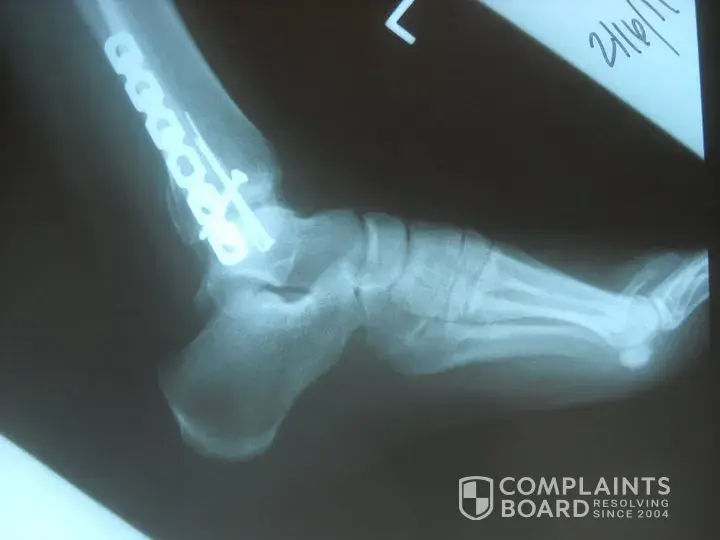

Two weeks after purchase... shattered my ankle breaking the tibia, fibula and talus. Interesting part is we had just had a health fair and my bone density came back great. Simply turned to open the back of a vehicle and foot stayed planted but leg gave. Surgey (5 pins, plate and additional screw), 34-36 visits to physical therapy, still ice 6 months later...